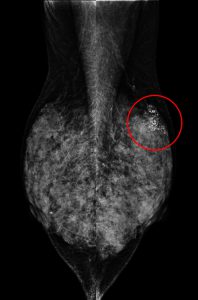

一、乳房X光攝影檢查

國際公認最有效降低死亡率的篩檢工具,偵測乳房內「微鈣化點、局部組織變形」。台灣研究顯示:每二年接受1次乳房攝影檢查,可降低乳癌死亡率41%、減少30%的第二期以上乳癌發生率。目前國健署補助45~69歲女性、40~44歲二等親內有乳癌家族史之婦女「每二年一次免費乳房攝影檢查」。但對於亞洲女性高比例的緻密型乳房(高比例乳腺組織),乳房攝影的診斷率較差(對最緻密型乳房靈敏度僅30~48%),須合併「乳房超音波」檢查增加診斷率。

【個案分享】

(A)

(B)